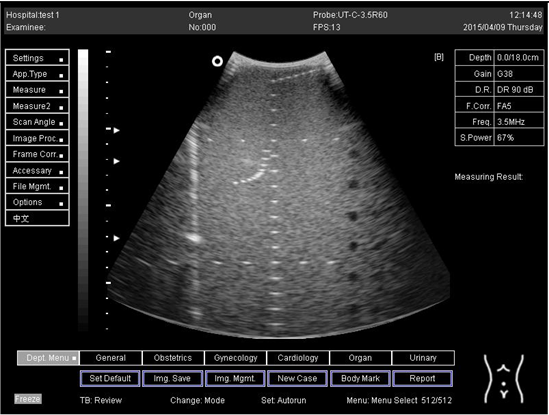

In the current experiment, tissue-simulating phantom quality assurance was applied to examine the performance and accuracy of the ultrasound imaging device (Figure 1). The phantom simulates the acoustic features of real tissue and supports the measurement of structures in an encouraging environment. The imaging system can detect any alterations in performance that happen during the ordinary lifetime of imaging system parts. Thus, routine examination control is able to minimize the time of repeat scans and maintenance duration.

The tissue-mimicking phantom and diagnostic imaging systems are calibrated at room temperature (23 °C). Therefore, measurements need to be made at the normal temperature. The multipurpose phantom (phantom model 539), on the other hand, is used to hold the test and is designed to provide the operator with an all-inclusive way of examining the capability of the linear array, annular array, sector, phased array, and diagnostic technique. Several significant ultrasound device functions must be understood while conducting this research study. These properties are essentially global to all medical ultrasound instruments.

The model 539 multipurpose phantom is an easy, comprehensive means of evaluating imaging systems over the full range of clinical imaging frequencies (2 MHz to 18 MHz). This phantom is designed with a combination of monofilament line targets for distance measurements and tissue mimicking target structures of varying sizes and contrasts. Cystic-like target structures are positioned in-line vertically, thereby permitting an entire target group to be displayed in one view. Due to the acoustic similarity of the background material and the target structures, artifacts caused by distortion, shadowing or enhancement are eliminated. Six gray scale targets ranging in contrast from +15 to −15 dB are provided to evaluate the system’s displayed dynamic range and gray-scale processing performance. All ATS urethane phantoms are guaranteed for the useful life of the phantom, defined as 10 years.